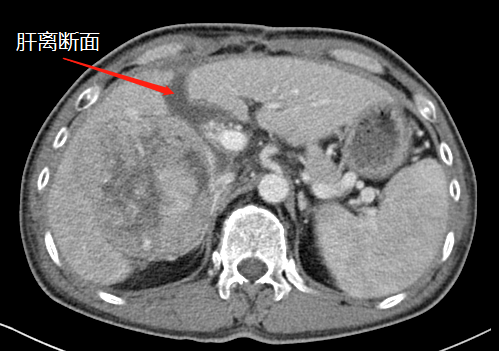

術(shù)前,左肝體積很小

第一次術(shù)后,結(jié)扎門靜脈劈開肝臟

“9月底,在第一階段手術(shù)中,我們先將患者的右側(cè)門靜脈結(jié)扎(肝的血液供應(yīng)通過門靜脈和肝動脈進(jìn)行),保留肝動脈、肝靜脈和膽管的完整性,然后沿肝中裂將肝臟的左右葉徹底劈開?!睋?jù)胡偉介紹,人體肝臟具有很強(qiáng)的再生功能,結(jié)扎門靜脈右支后左側(cè)肝臟由于過量的血液供應(yīng)短期內(nèi)迅速增大;同時將患者的左右肝臟離斷,降低了腫瘤侵犯左側(cè)肝臟的可能。